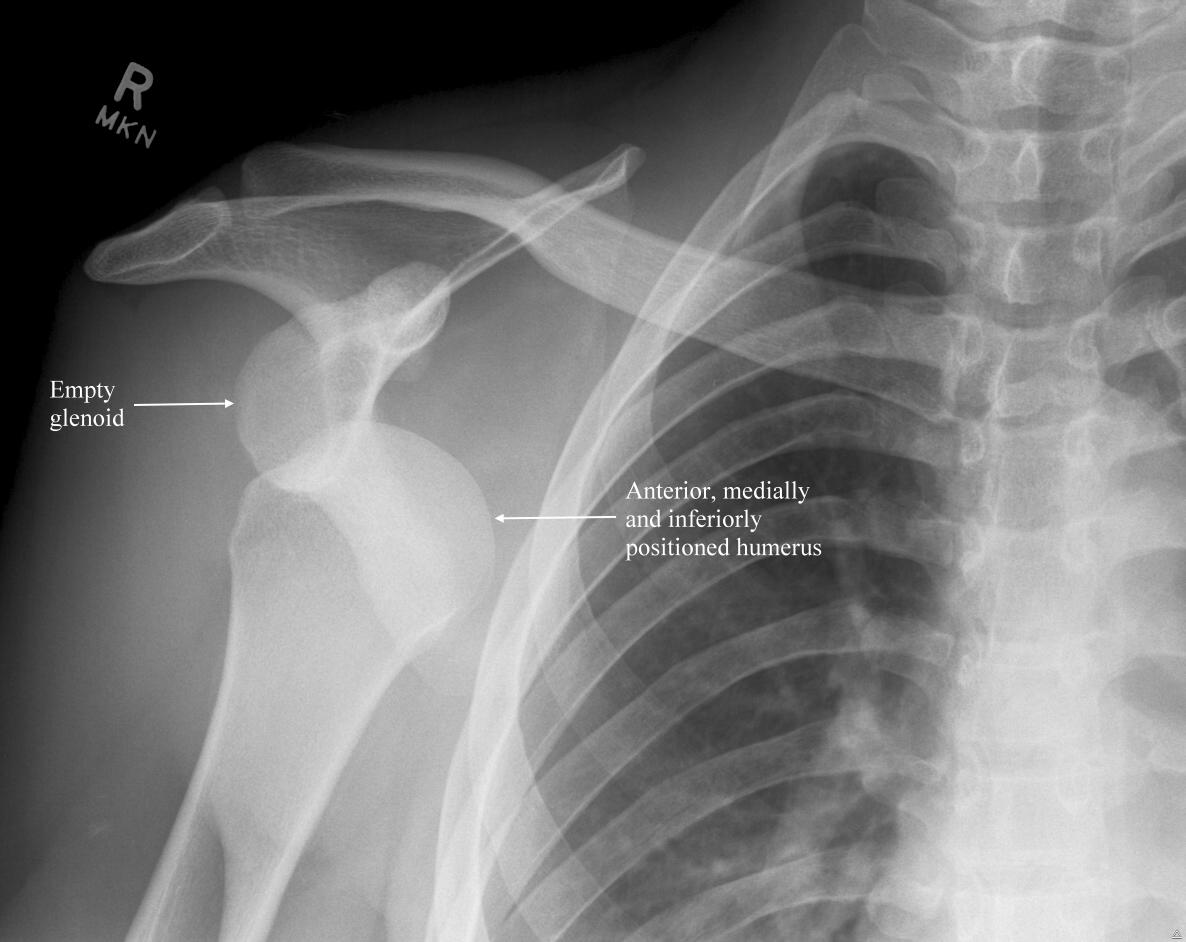

About nine months ago, I dislocated my shoulder while working out with a personal trainer. Unfortunately, this was not a new thing (to the left shoulder it was!) so, initially, I felt like– okay, I can manage this. We just need to get it back into place as I’d been able to self reduce my right shoulder before.